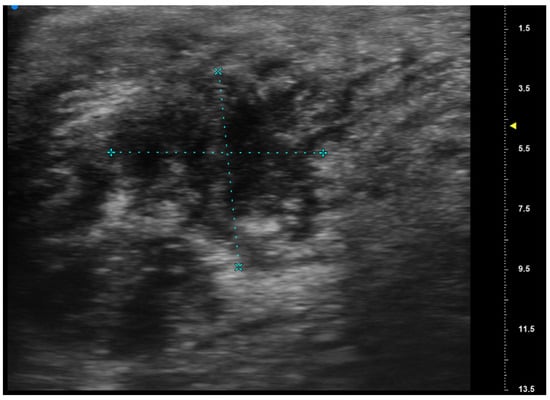

Reliability of Ultrasonographic Assessment of Depth of Invasion and Tumor Thickness in Intraoral Mucosa Lesions: A Preliminary Experience

2.2. UHFUS Scan Protocol